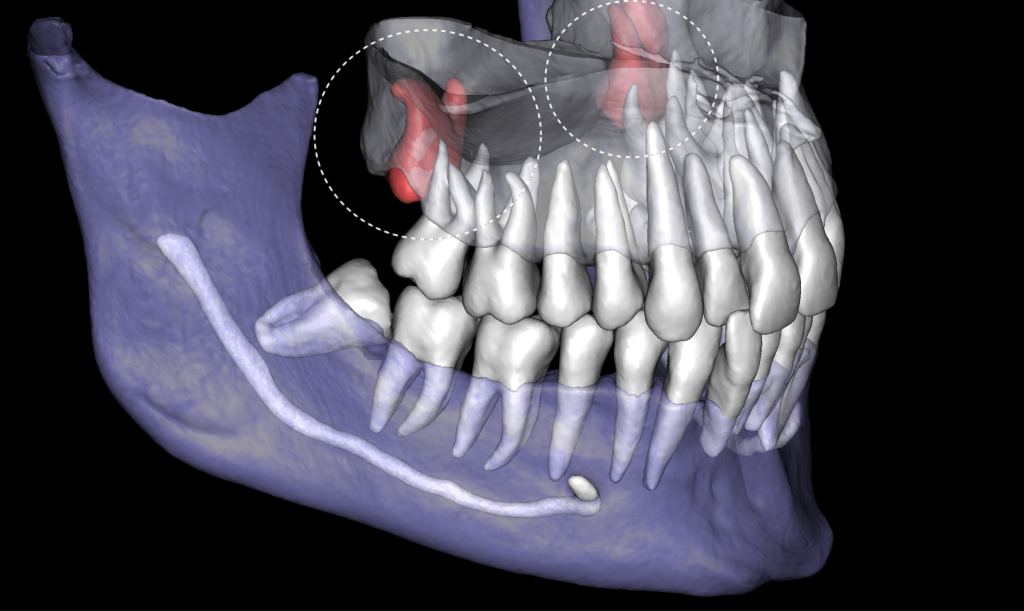

Extracting upper third molars can be difficult, if they are impacted and in contact with the maxillary sinus. Diagnocat AI will help you carefully plan your procedure, minimizing the risk of possible complications.

The “Third Molar Report” is a tool created by Diagnocat AI, it creates an optimal 3D visualization which helps to assess the position of the roots of the third molars relative to the roots of adjacent teeth and the floor of the maxillary sinus.

Teeth 18 (Universal 1) and 28 (Universal 16) were removed with minimal surgical trauma and without causing damage to the maxillary sinuses.